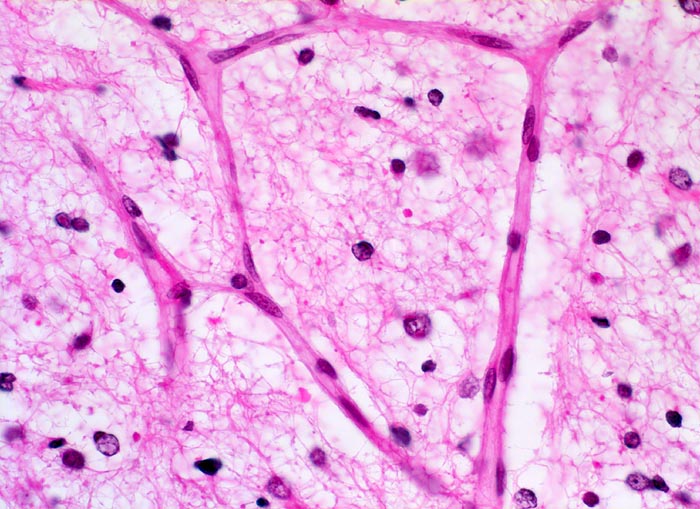

PathoPic ID 5260 - Oligodendrogliom (WHO Grad II)

Oligodendrogliom (WHO Grad II)

maligner Tumor

Hirn frontal

Nervensystem

Das Tumorgewebe wird von einem feinen Netzwerk verzweigter Kapillaren durchzogen

Kopfschmerzen und epileptische Anfälle seit zwei Jahren.

Histologie

400

59

männlich